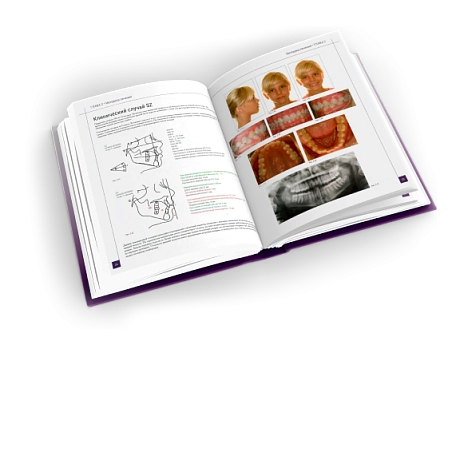

Корректор класса II Вильямса (исполнение 3) - Набор 320-0100

Описание товара

Характеристики